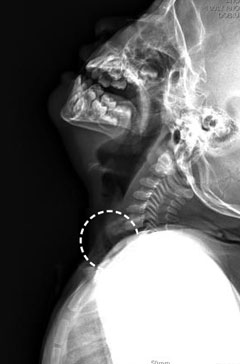

크룹증후군으로 기도가 좁아져 있는 소아의 엑스레이 사진(동그라미 안). /상계백병원 제공

크룹증후군은 추운 겨울 3세 미만 영유아에게서 자주 발생하는 질환으로, 상기도(후두)가 좁아지는 게 특징이다. 파라인플루엔자나 RSV(호흡기세포융합바이러스) 등에 감염돼 생기는데, 상기도가 선천적으로 좁아 생기는 경우도 있다.